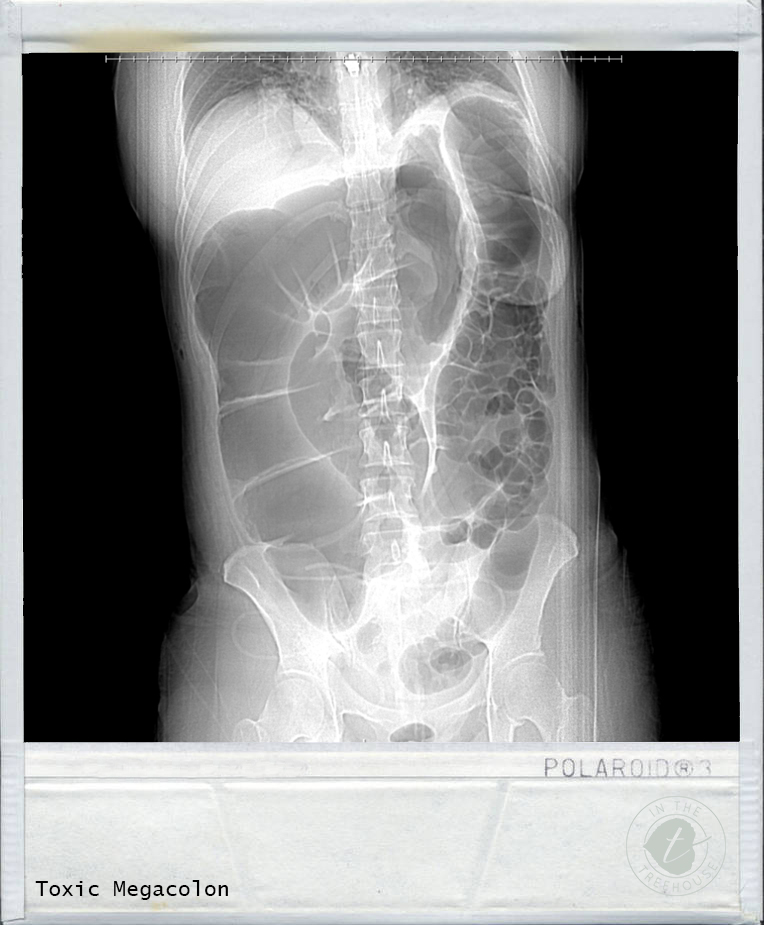

My sister took over watching our kids so my parents could be there while I was in surgery. The plastic surgeon came up to the hospital and sat with Chad throughout the surgery/recovery. I was very touched when I learned about that. Chad learned that after the first surgery, my bowels never woke back up. I had severe ileus. While my intestines were sleeping so to speak, they sort of flattened out inside my body. Somehow, that caused a little kink, and at some point, my intestines started filling up with gas. The large bowel was most pronounced at the cecum which measures 12.1 cm. I developed Toxic Megacolon. Look that up online and you will see some scary stuff!

The surgeon went through the horizontal incision. He removed the mesh from the hernia repair, and he had to cut through all of the stitches for the muscle repair. You know those prank cans that have a snake that comes shooting out when you open it? The surgeon said my intestines came shooting out in that same fashion once he cut me open and cut through the layers. There was just so much pressure built up inside and it was looking for the quickest way out.

He told Chad that he had to remove my appendix and a foot of my colon that perforated. He used a sausage analogy to describe the perforation. He said when you are cooking sausage, you will notice as it heats that the outer skin will pull apart and sort of rip. The built-up pressure caused that outer layer of the colon to rip and pull apart. Once that happens, that part of the colon is no longer any good.